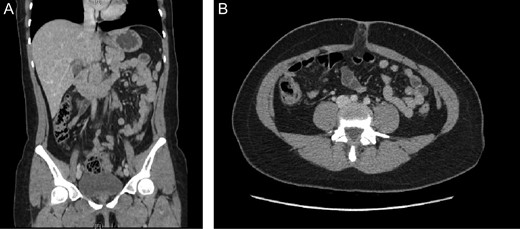

Patient is a 29-year-old woman without any past medical history, she presented to the emergency room with a 2-day history of abdominal pain and nausea, the pain first appeared on the epigastric region but in the last 12 hours the pain became more severe and migrated to the right lower quadrant. There were no accompanying symptoms such as dysuria or diarrhea. On clinical examination, a dehydrated and febrile patient was encountered, her abdomen was sensitive to gentle pressure and diffuse pain was discovered in her lower abdomen. Laboratory exams revealed mild leukocytosis with neutrophilia. Due to her condition and to rule out other surgical causes, a contrast-enhanced computed tomography (CT) revealed a distended cecum, a slight amount of free liquid in her abdomen and an inflamed appendix. The proximal third of the appendix measured more than 6 mm (Fig. 1A and B).

(A) Contrast-enhanced CT, revealing an inflamed appendix. (B) Contrast-enhanced CT, surrounded by heterogeneous inflamed fat.